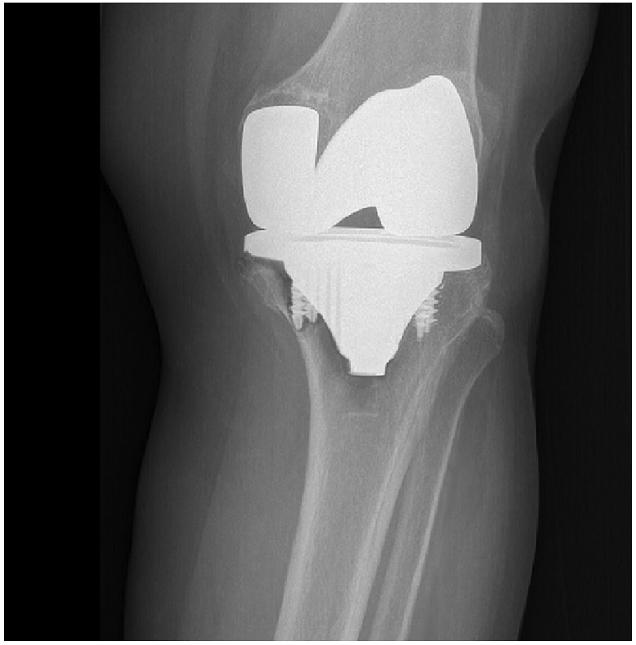

A total of 51 knees of 49 patients (33 female and 16 male; mean age: 61.6 years (range, 29-66 years)) who underwent TKR surgery with a posterior stabilized hydroxyapatite coated knee implant were included in this study. All of the tibial components were fixed with screws. The HSS scores were examined preoperatively and at the final follow-up. Radiological assessment was performed with Knee Society evaluating and scoring system. Kaplan-Meier survival analysis was performed to rule out the survival of the tibial component.

The mean HSS scores were 45.8 (range 38-60) and 88.1 (range 61-93), preoperatively and at the final follow-up respectively. Complete radiological assessment was performed for 48 knees. Lucent lines at the tibial component were observed in 4 patients; one of these patients underwent a revision surgery due to the loosening of the tibial component. The 10-year survival rate of a tibial component was 98%.

Cementless total knee replacement has satisfactory long term clinical results. Primary fixation of the tibial component with screws provides adequate stability even in elderly patients with good bone quality.

方法

本研究纳入了49例患者的51个膝关节(33例女性和16例男性;平均年龄:61.6岁(范围,29 - 66岁)),这些患者接受了后稳定型羟基磷灰石涂层膝关节假体的全膝关节置换术。所有胫骨组件均用螺钉固定。术前和末次随访时检查HSS评分。采用膝关节协会评估和评分系统进行影像学评估。进行Kaplan-Meier生存分析以排除胫骨组件的生存率。

术前和末次随访时的平均HSS评分分别为45.8(范围38 - 60)和88.1(范围61 - 93)。对48个膝关节进行了完整的影像学评估。4例患者观察到胫骨组件处有透亮线;其中1例患者因胫骨组件松动接受了翻修手术。胫骨组件的10年生存率为98%。

结论